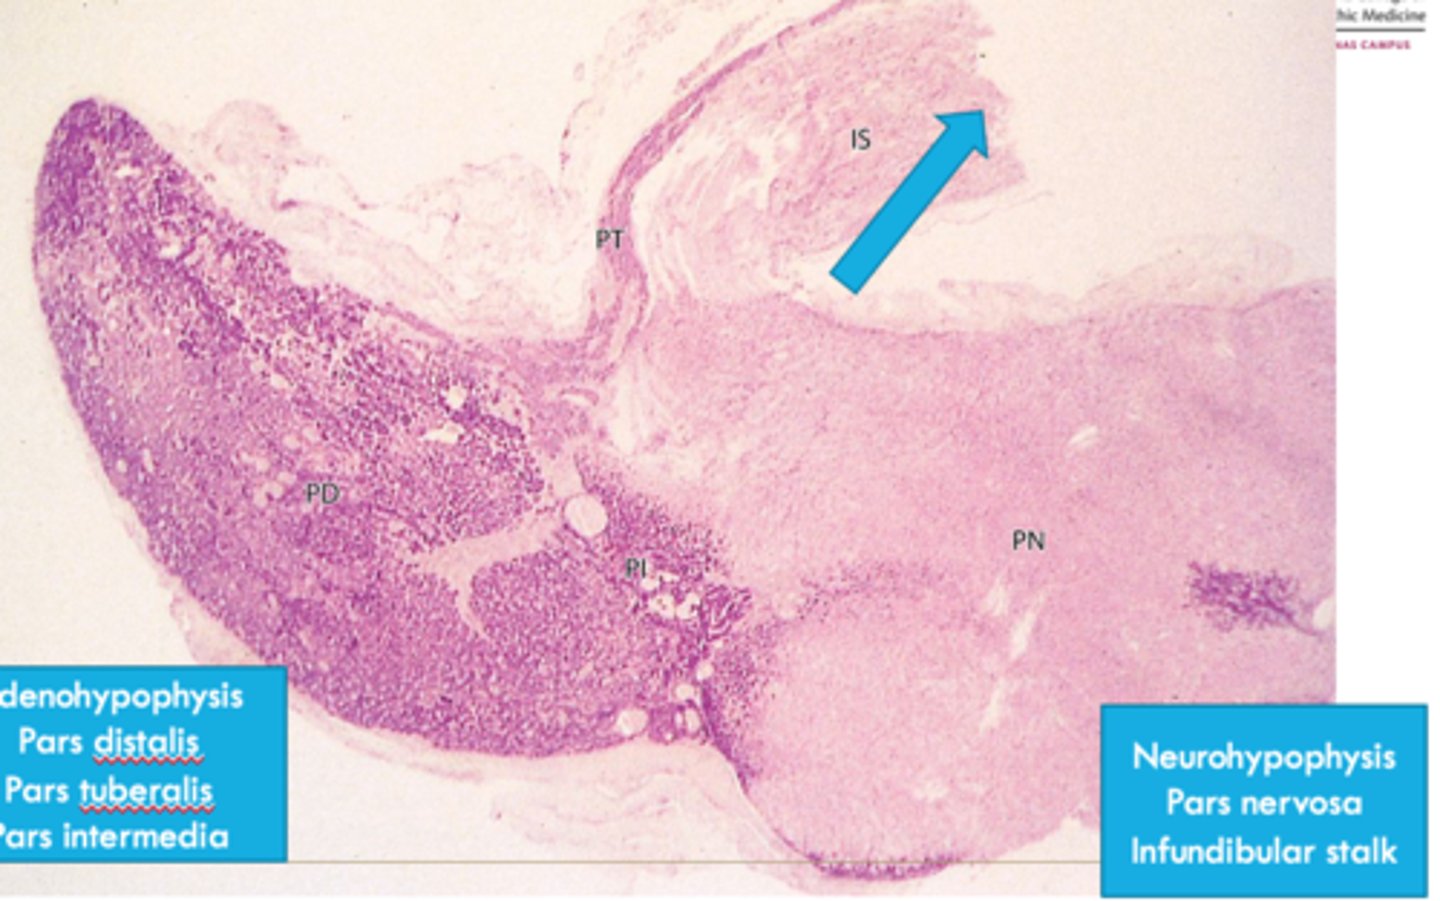

paraventricular (oxytocin) and supraoptic (ADH)

axons from the ______ and _______ nuclei of the hypothalamus extend through the infubdibulum into the posterior pituitary

-then released into capillaries from the posterior pituitary

superior hypophyseal artery

delivers blood to the capillary network in the median eminence and infundibular stalk

inferior hypophyseal artery

blood supply to the neurohypophysis

hypothalamic/hypophyseal portal system

function of ________________ ______ ________:

-Carries neuropeptides from median eminence to neurohypophysis where they can stimulate or inhibit hormone release

posterior pituitary

this part of pituitary does not contain the cells that synthesize its hormones

-ADH and oxytocin come from nuclei from hypothalamus

ADH and oxytocin

hormones released from posterior pituitary